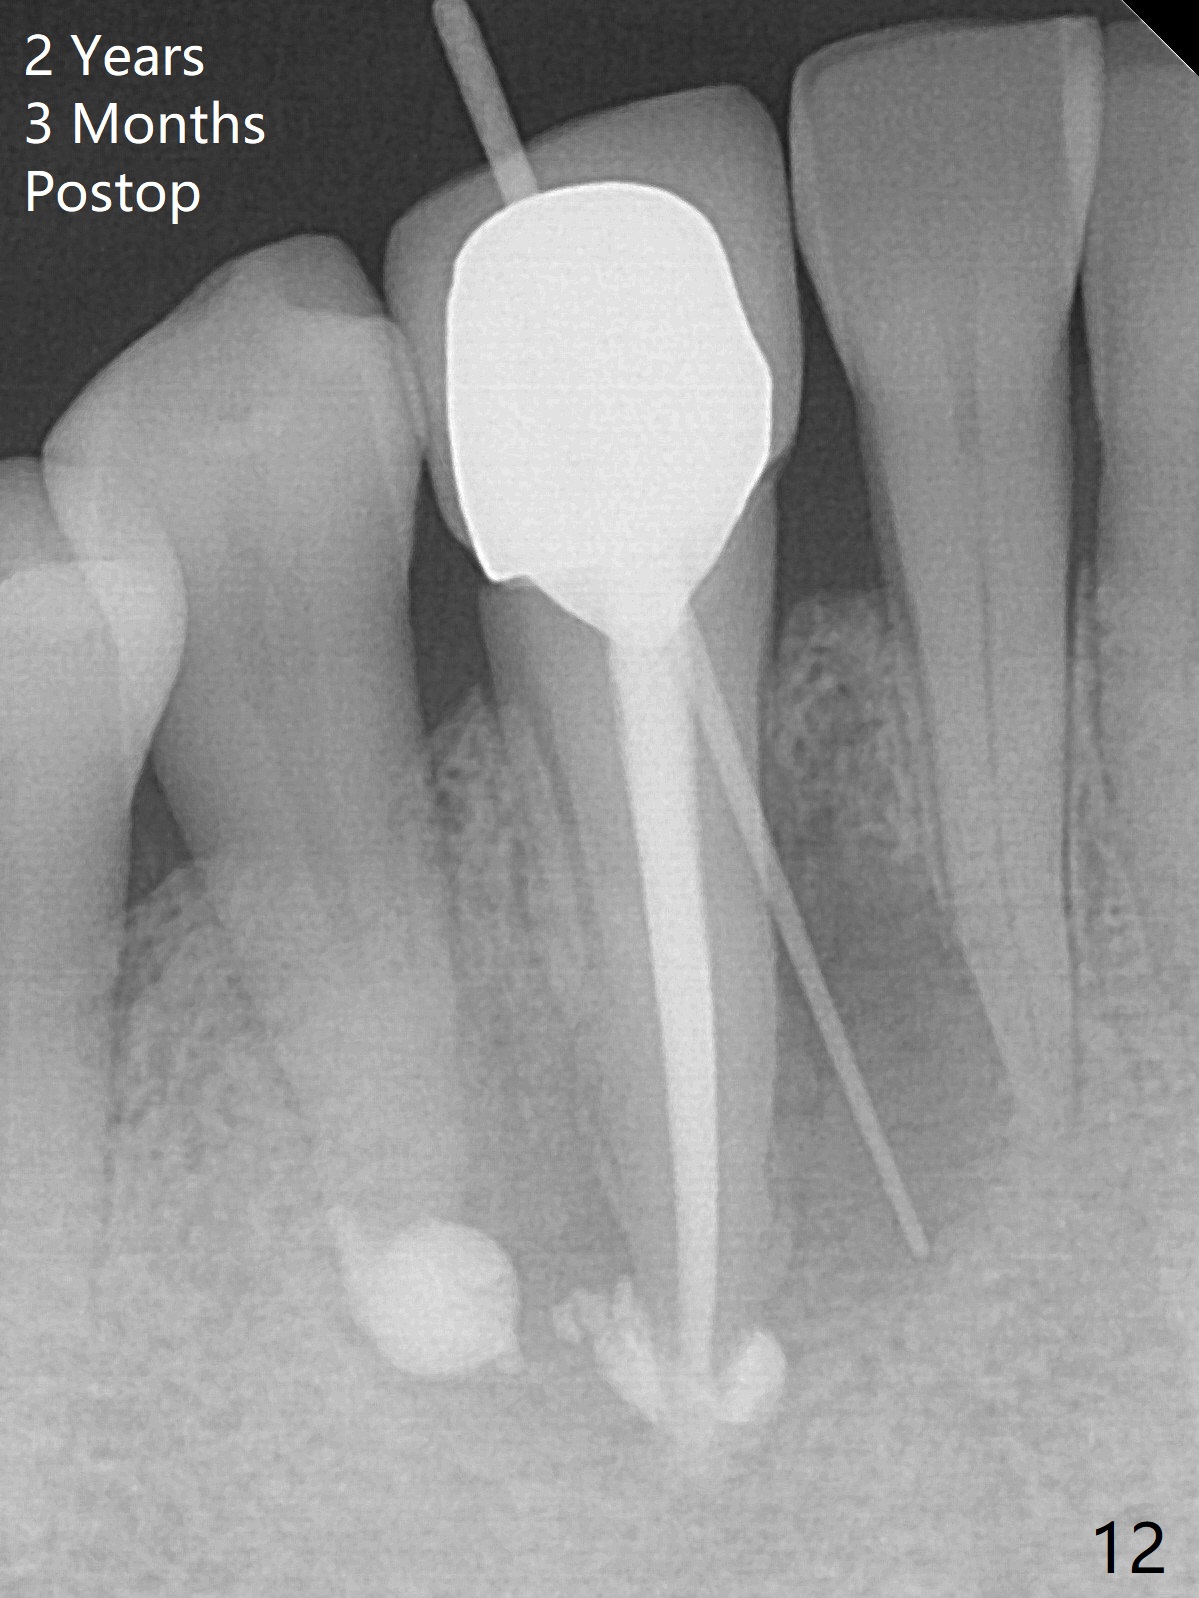

The patient reports that the fistula disappears after initial RCT at #27, but it seems to re-appear 1 month post canal debridement (Fig.5 >). After repeated debridement with #40 hand file at 23 mm, apply Endo Sequence BioCeramic Sealer and insert GT 40/.08 master cone with black carrier (Fig.6). One hour later, the patient returns with re-appearance of the fistula (Fig.7). Following local anesthesia, poking the fistula leads to sealer escape (Fig.8). After debridement of the fistula until the bone, PA is retaken (Fig.9). A crown was made in China; mesial radiolucency starts (Fig.10). The tooth remains asymptomatic 1 year 5 months postop (Fig.11). There is a lingual fistula with enlarged mesial radiolucency 2 years 3 months postop (Fig.12-14).